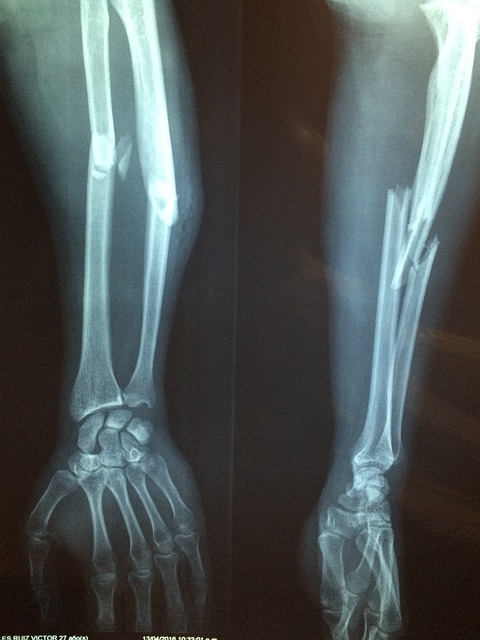

연골은 관절을 보호하는 부드러운 조직으로, 관절의 원활한 움직임을 돕고 충격을 흡수합니다. 연령 증가, 부상, 또는 특정 건강 상태로 인해 연골이 손상되거나 마모될 수 있으며, 콘드로이친은 이러한 연골의 손상을 늦추거나 관절 건강을 개선하는 데 도움을 줄 수 있습니다.

- 연골 손상 완화: 콘드로이친은 연골 세포의 새로운 성장을 촉진하고 연골 분해를 억제함으로써 연골 손상을 줄이는 데 도움을 줍니다. 이는 연골 마모를 늦추고 장기적으로 관절의 건강을 유지하는 데 기여할 수 있습니다.